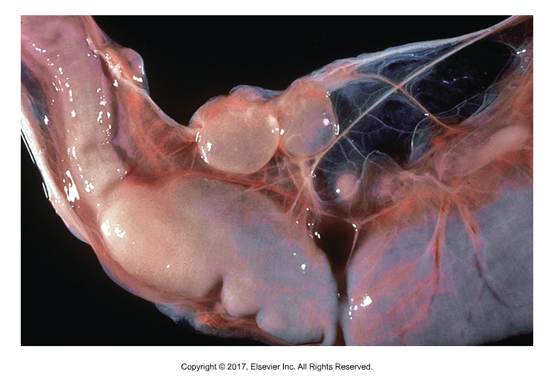

Multiceps sp. metacestode stage

Forms coenurus that is found in sheep or rabbit intermediate host

Coenurus cerebralis (M. multiceps) or Coenurus serialis (M. serialis)

Single large bladder with several scolices attached to the wall

Unique in that many tapeworms mature from each coenurus, one for each scolex

In sheep, hexacanth embryos are ingested and larvae (5cm) migrate to nervous system (brain or spinal cord) and can produce neurological symptoms in infected sheep